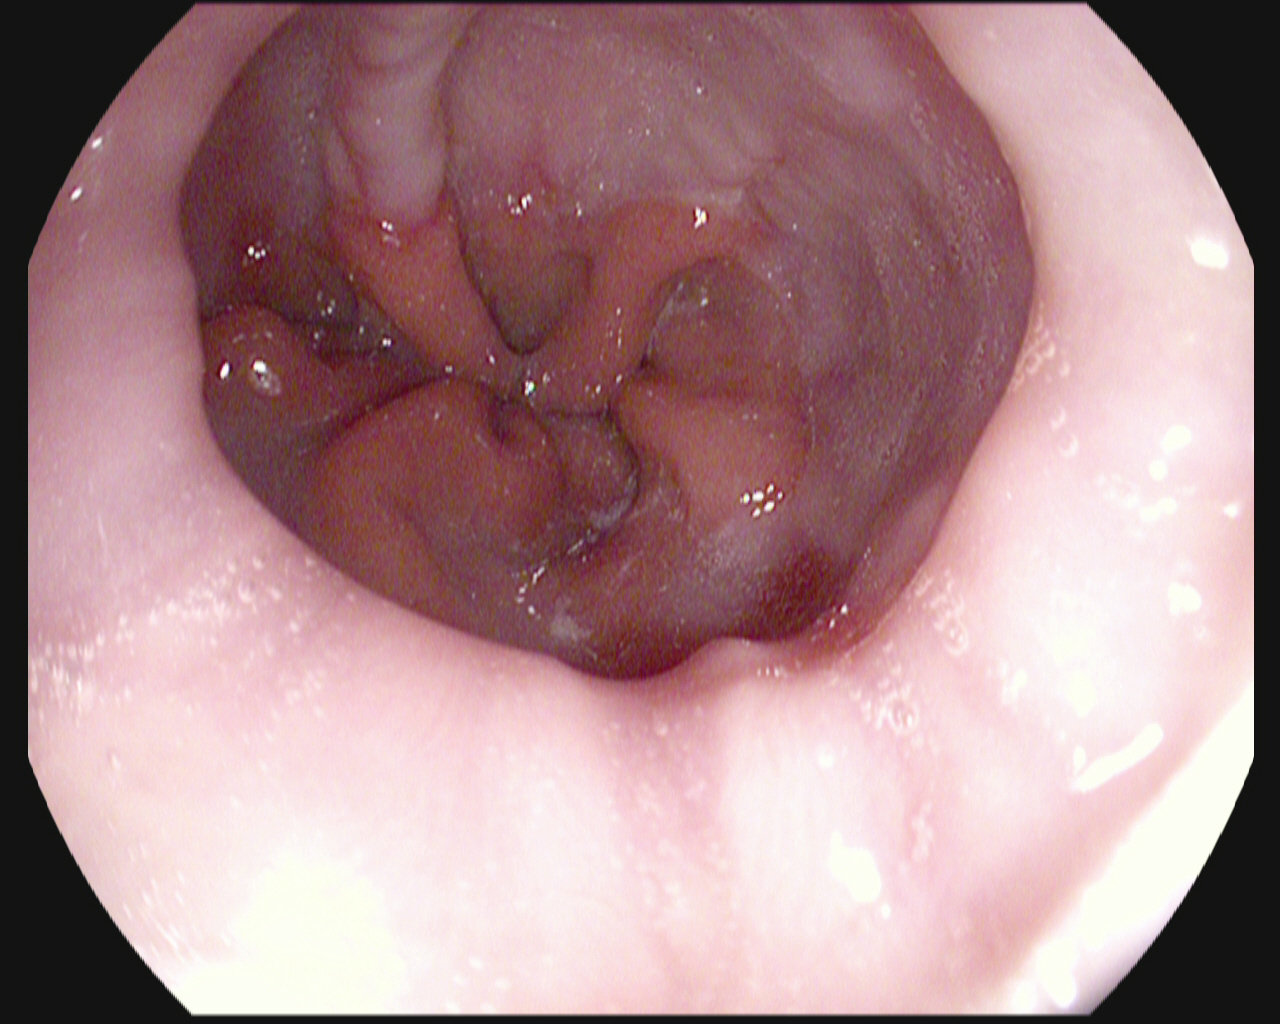

The Nerthus Dataset

BBPS 3

BBPS 2

BBPS 1

BBPS 0